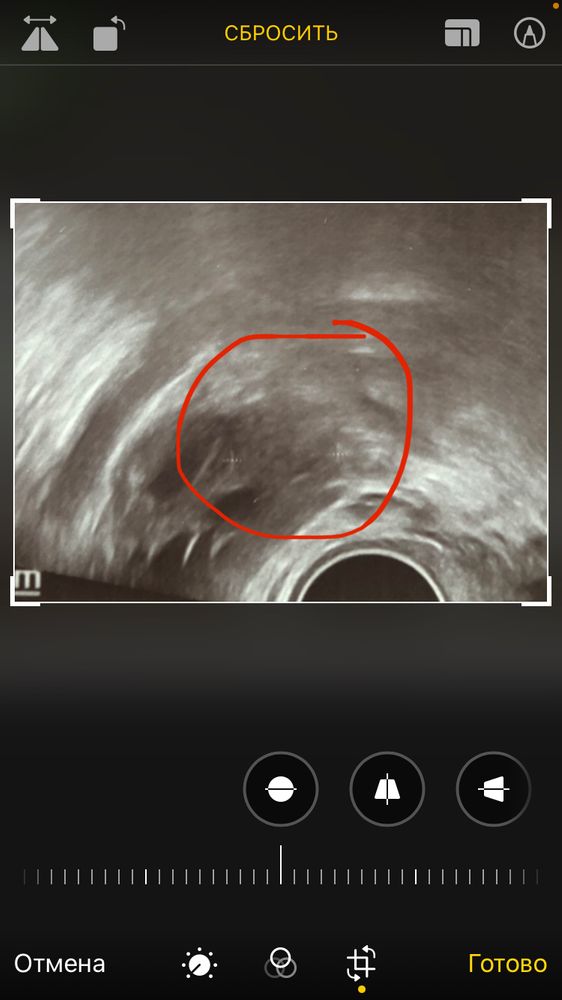

Была ли овуляция? 🧐

Я думаю будет двойная овуляция. Одно ЖТ нашли на 13 ДЦ, второе ЖТ будет на 16-17 ДЦ

Ната, а это вообще ЖТ? То, что там нашли? И почему тогда не выросла БТ-шка? Из-за второй овуляции?

Яна, температуру никогда не отслеживала, не знаю про неё ничего. Я доверяю только УЗИ. По первому УЗИ у вас нашли ЖТ и доминантный фолик. Этот же фолик, как я понимаю, лопнул на 16 ДЦ. Первое ЖТ стало почему-то меньше правда, но тут разные узисты, поэтому погрешность допускаю. У меня в этом цикле тоже двойная О. ЖТ абсолютно разные по величине (разница в О в несколько дней), но какое первое, какое второе не знаю. Эндометрий просто огромный, аж 16 мм😏 И теперь из-за двойной овуляции у меня задержка (тест отрицательный).😐 Предполагаю, что вторая О была на 17-18 ДЦ, вместо 14, поэтому всё и сместилось, ну либо киста выросла. Завтра на УЗИ узнаю.